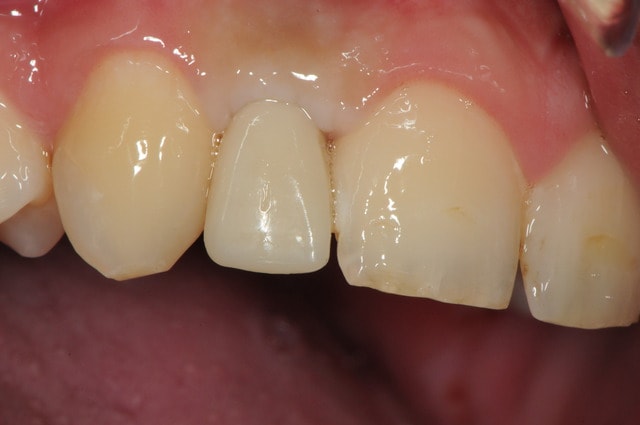

-1 ou 2 mois plus tard ( je sais plus)

- empreinte avec transfert pop in

- pilier zircone esthétique Axiom

- prothèse et pilier

- pilier zircone en place

- couronne en place (petite compression gingivale)

fin du traitement